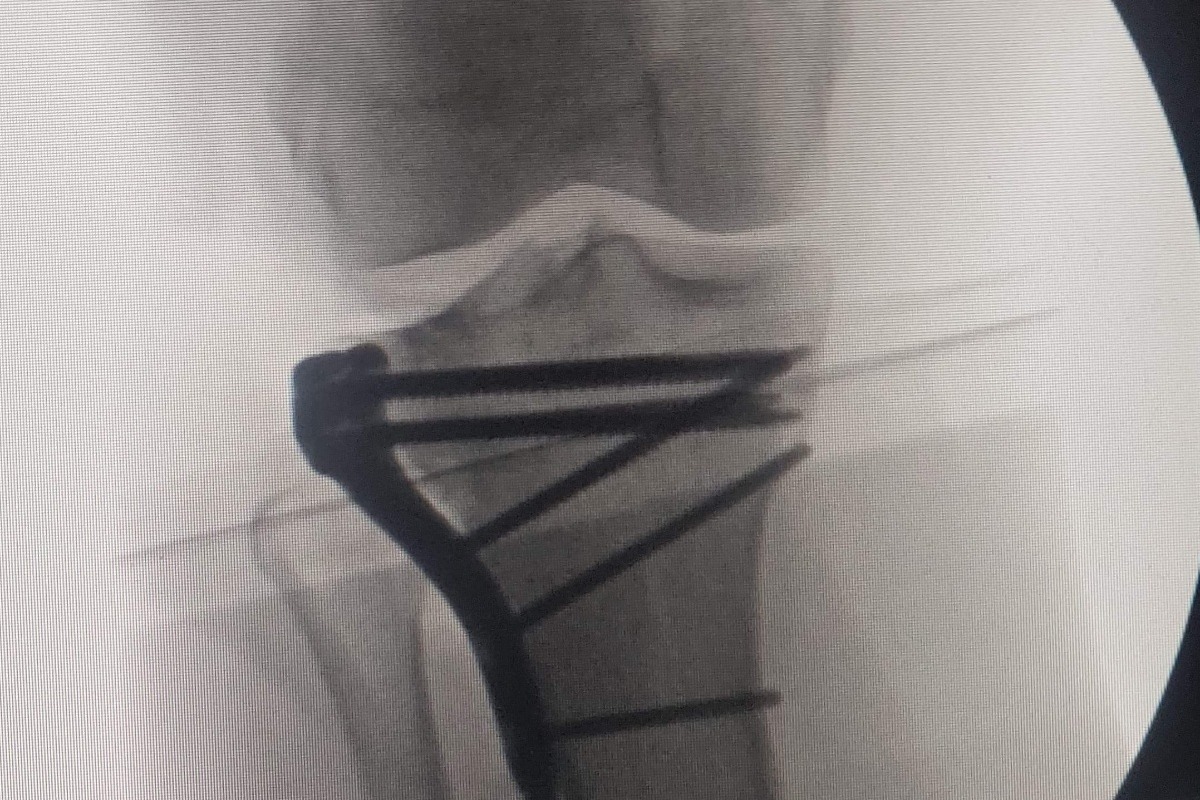

Finally making it to the ambulance. After stabilizing Kim, she was transferred to Sierra Vista. We know she has a broken sternum, shattered tibia, broken fibula, small brain bleed and a very large hematoma on the left side of the chest. The surgery cant take place until she is stable enough to go under. Jimmy will need reconstructive surgery on his leg . As for the DRUNK DRIVER he was ARRESTED before taken by ambulance for major injuries. It hard to rationalize life can be taking in a heartbeat. Especially during these times when most cant even visit their loved ones. We are very very grateful they are still alive. They will be out of work for a while. With major medical bills and multiple surgeries to come, We don't know if the DRUNK DRIVE was even insuranced. Any amount donated will be greatly appreciated. We know times are tuff right now. All donation will be going to relieve the financial burden that has been unfortunately bestowed upon Kim and Jimmy. Right nowhttps://www.ksby.com/news/local-news/head-on-vehicle-collision-reported-near-cholame-y-intersection-east-of-paso-robles